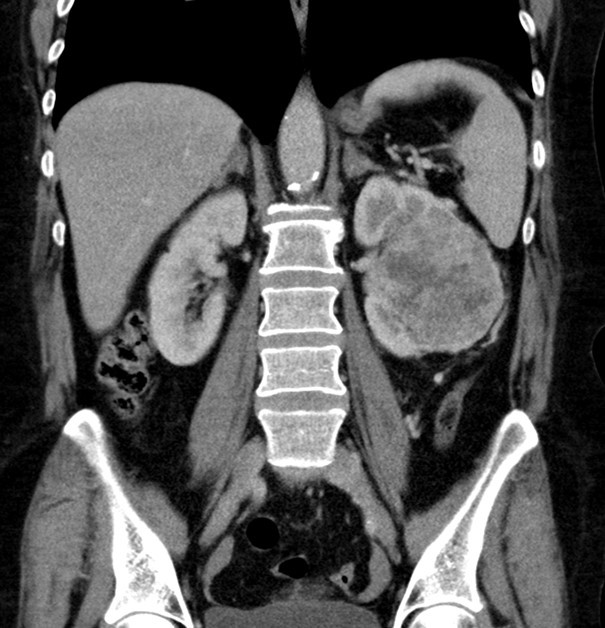

CT vyšetření ledvin provedené za sedm dní od indikace potvrdilo nález tumorózní expanze v levé ledvině. Morfologická struktura tumoru vedla k podezření na světlobuněčný renální karcinom, bez patologické lymfadenopatie. Dále byl zjištěn adenom levé nadledviny a četné cysty jater (obr. 2).

Obr. 2 Nález na levé ledvině u pacientky z kazuistiky zjištěný pomocí CT.

CT – výpočetní tomografie